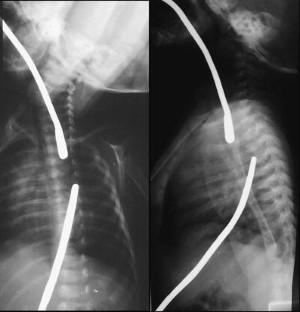

Between September 2001 and March 2004, five children were selected for treatment. Two of the children had esophageal atresia without fistula (type A) and three had atresia with fistula converted to type A surgically; however, surgeons failed to achieve an anastomosis because of the width of the gap. Neodymium-iron-boron magnets were used. Daily chest radiographs were taken until union of the magnets was observed. They were then replaced with an orogastric tube.

Fig. 1

Fig. 2